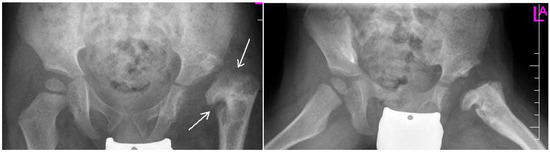

Figure 3.

Radiographs: AP and Lauensteun with postrezidual deformity in the same patient after 2 years.